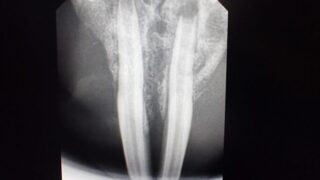

フクロモモンガの膀胱結石

フクロモモンガにも時に膀胱結石ができてしまいます。尿が出にくい、出血するなどあれば当院にご相談ください